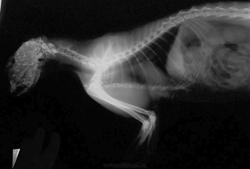

Данный снимок выполен через 8 лет, по другому поводу (рентген-неконтрастное инородное тело в гортани).

Выкладываю увеличенный фрагмент снимка и полный снимок.

А в этот раз решил съесть тропическое растение навроде алоэ с колючками по краям листьев, вот оно и застряло у него. Вытащили с третьей попытки.